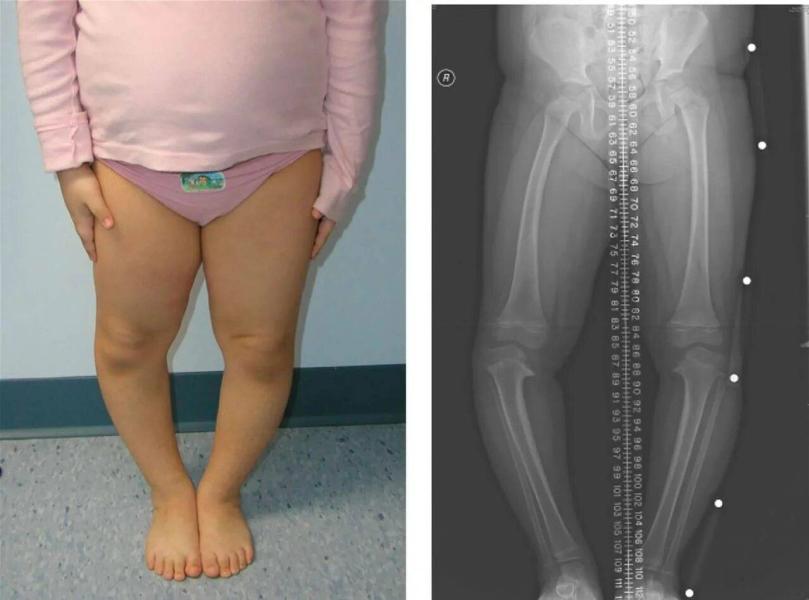

фото из интернета, для наглядности

А вам ставили варусную деформацию? Делали рентген? У нас сейчас также. Сколько на фото малышке?